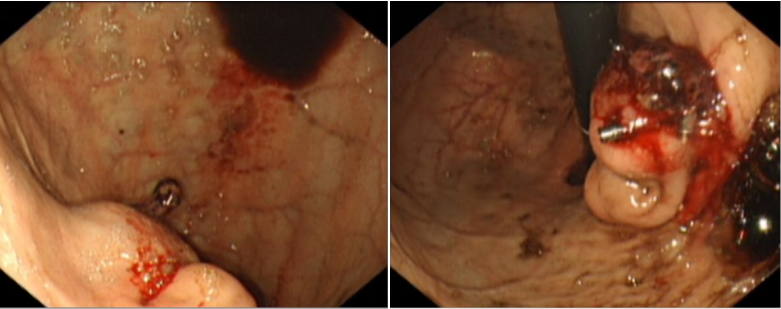

结合患儿的病史,高度怀疑间质瘤复发,胃镜下看到胃体小弯侧2处2厘米大小的粘膜下隆起病变,并看到自破裂的瘤体顶端,鲜血成滴状,不间断滴下。超声胃镜检查,提示:肿物内部回声不均匀,部分为低密度,部分为中密度,且病变与胃壁固有层连续。

因为间质瘤质地较脆,止血治疗过程中,再次出血加重的可能性极大,快速止血是亟待解决的问题。临床处理:于胃底处翻转镜身,在肿物不同部位和角度共使用3个钛铗夹闭后,出血停止。